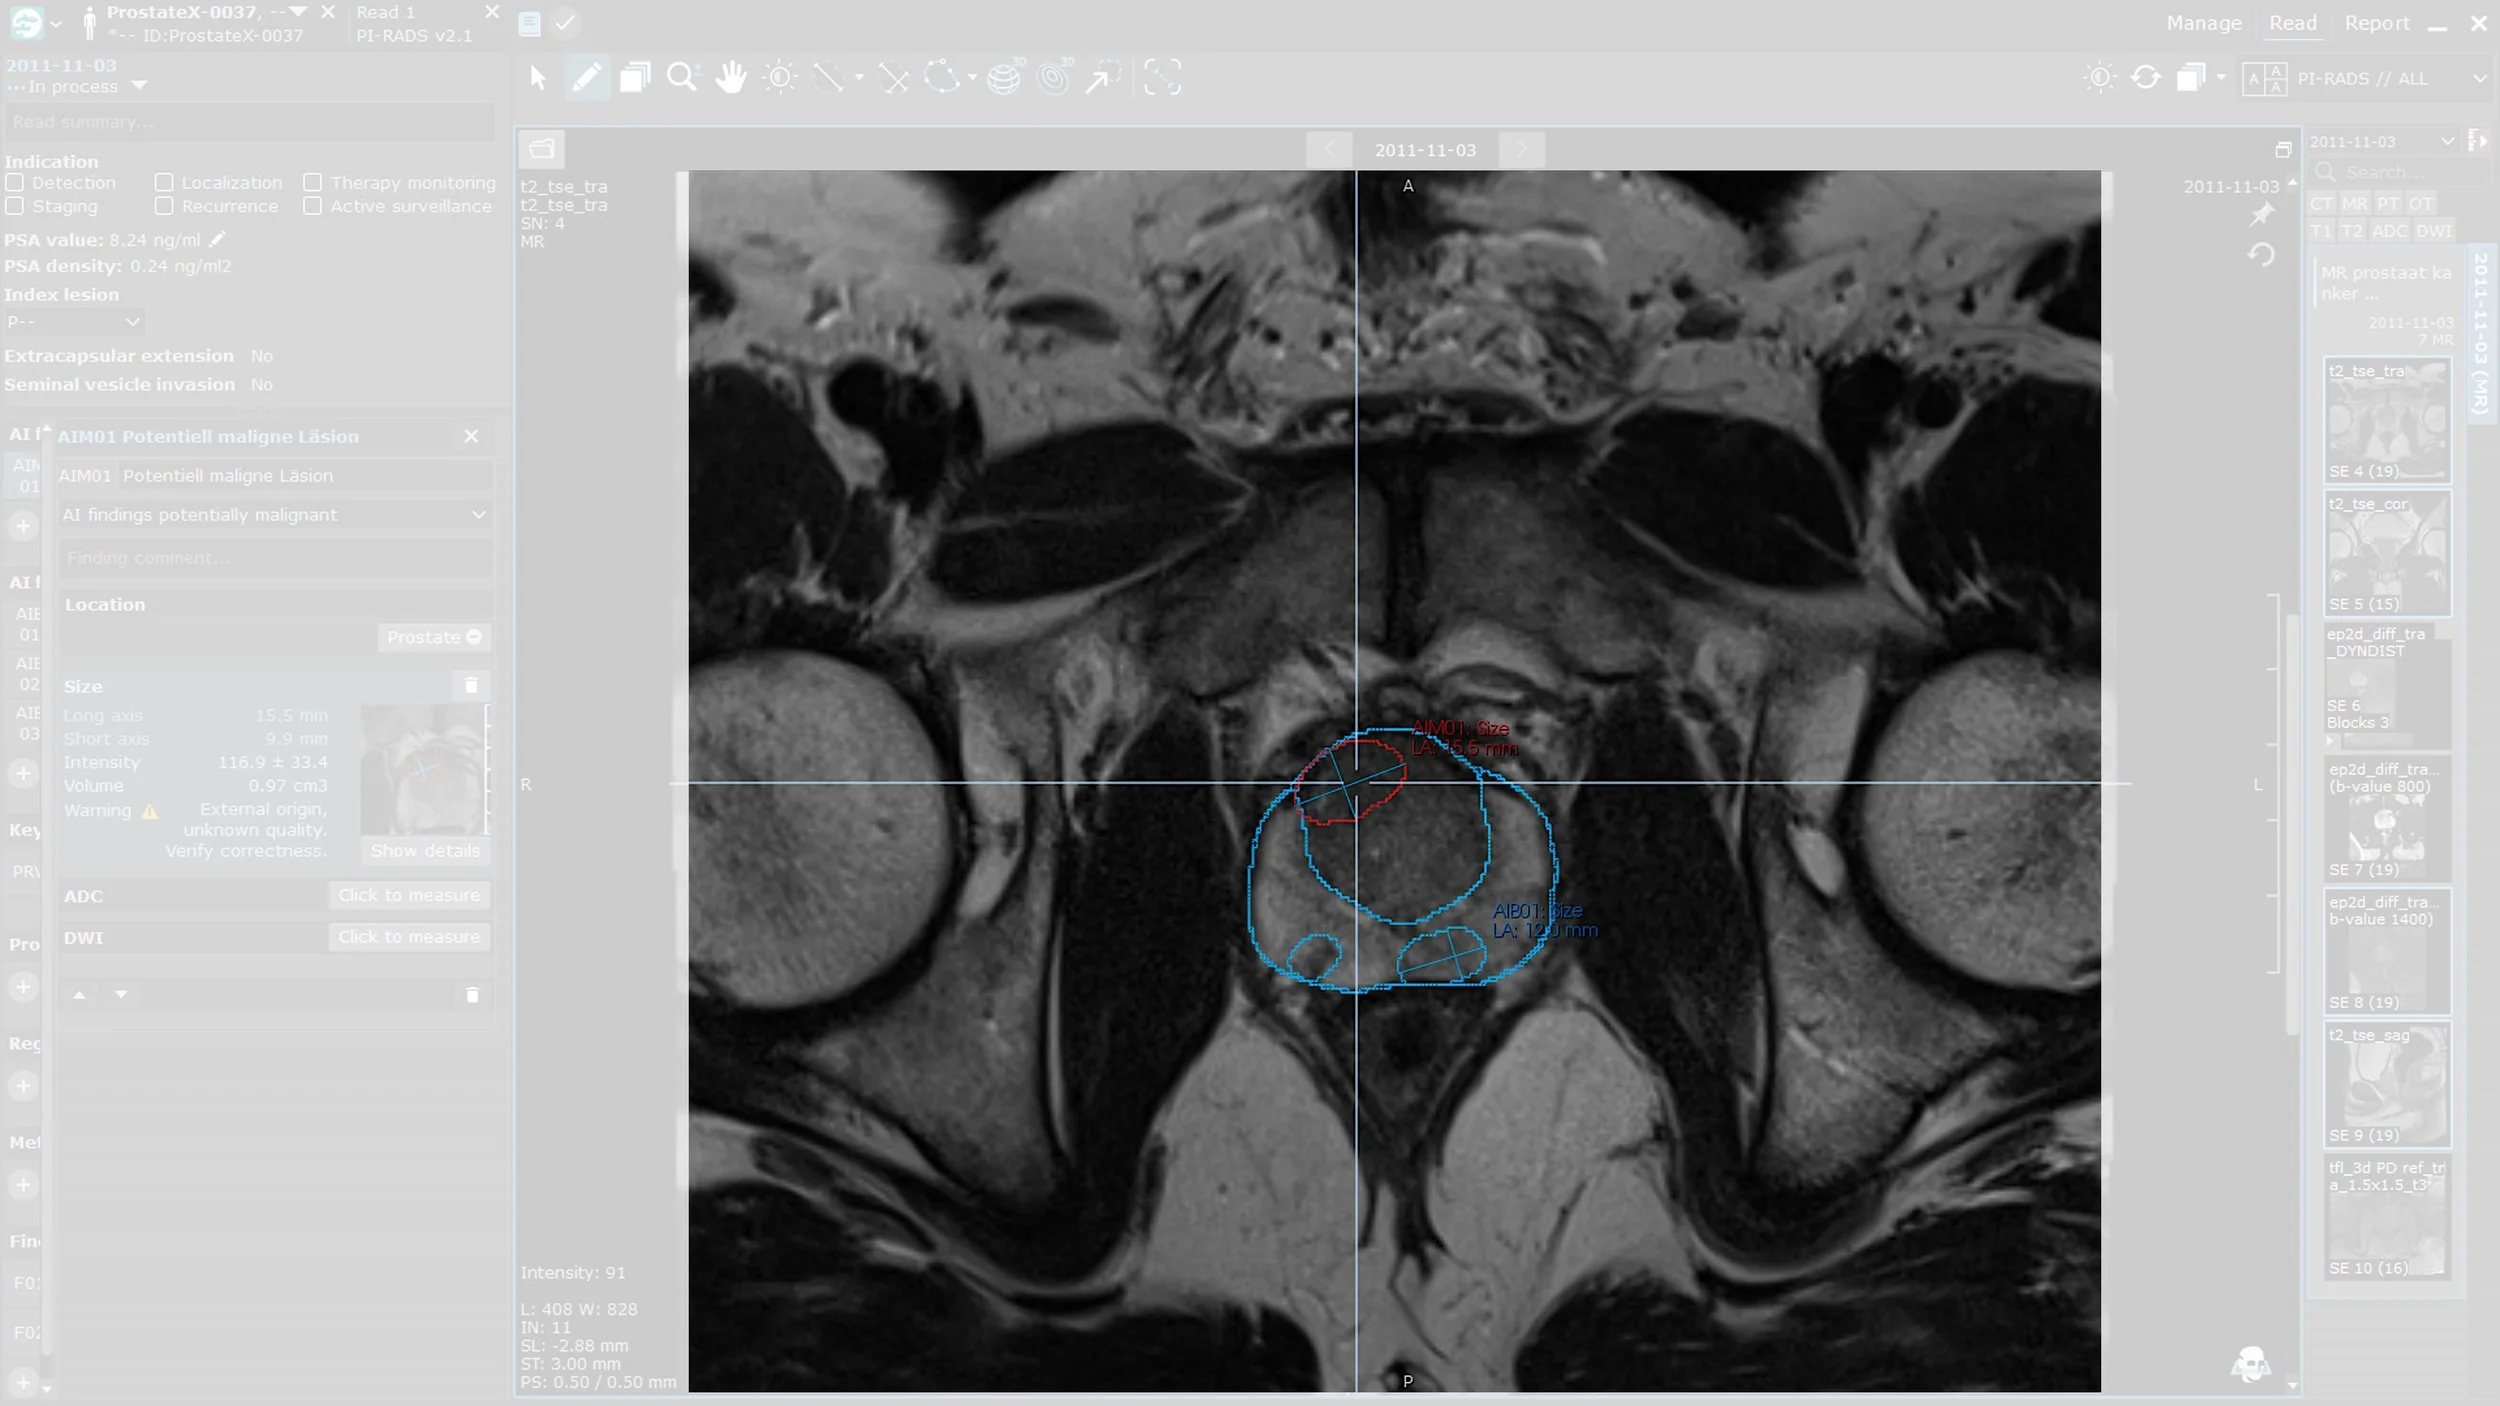

Prostate.Carcinoma.ai unterstützt Radiolog:innen bei der MRT-gestützten Diagnostik von Prostatakarzinomen. Zentrale Schritte im PI-RADS v2.1 Workflow werden automatisiert, die Bildanalyse beschleunigt und eine objektive, konsistente Zweitmeinung bereitgestellt.

Vollautomatische 3D-Segmentierung der Prostata und Prostataläsionen

Klassifizierung der Läsionen in potenziell gut- und bösartig

Voxel-genaue Volumenbestimmung von Prostata und Läsionen

Integriertes Plug-in für PACS bzw. Viewer Workstations